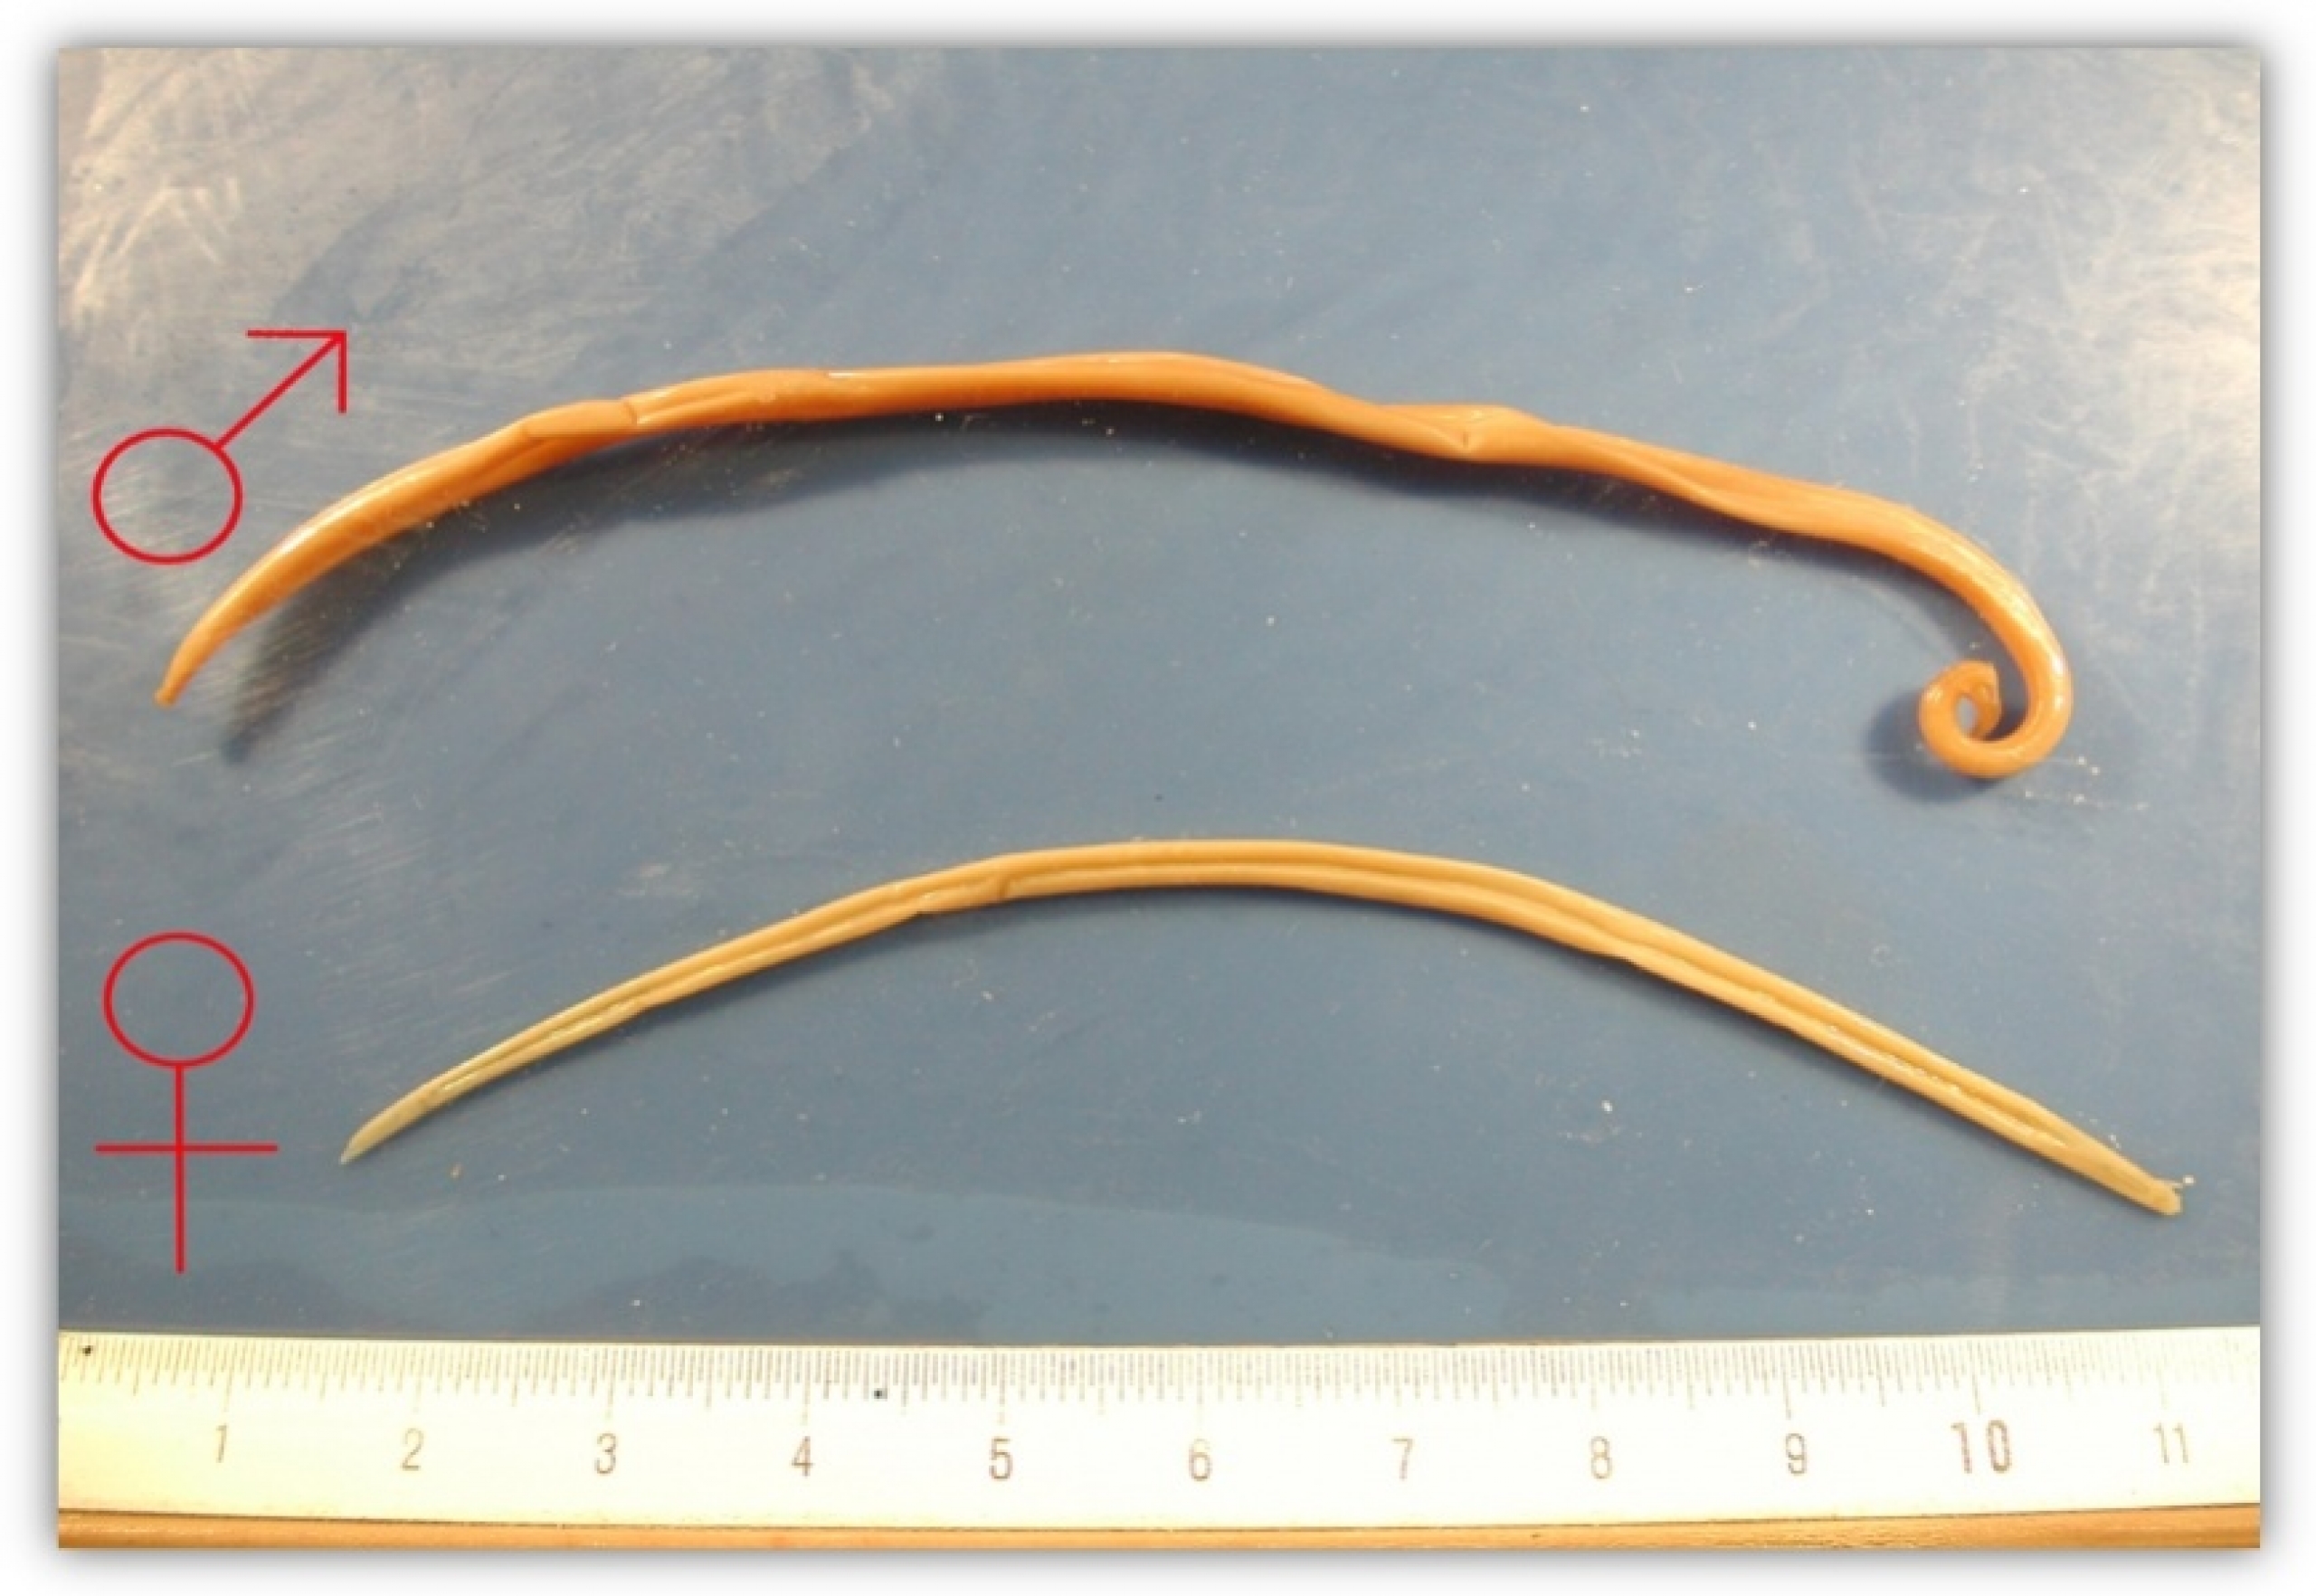

Фотографии нематод, цестод и трематод в природе

Раздел: Другие животные